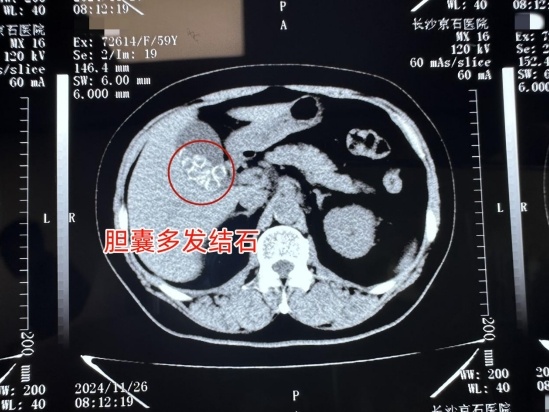

刘女士术前CT局部检查图

“通过患者术前CT的切片看,她的结石还是很多的,基本占了胆囊的二分之一。如果任由结石继续在胆囊内部,不仅会加重炎症,还有可能对胆囊功能造成不可挽回的严重后果。”长沙京石医院肝胆外科主任李小攀表示。